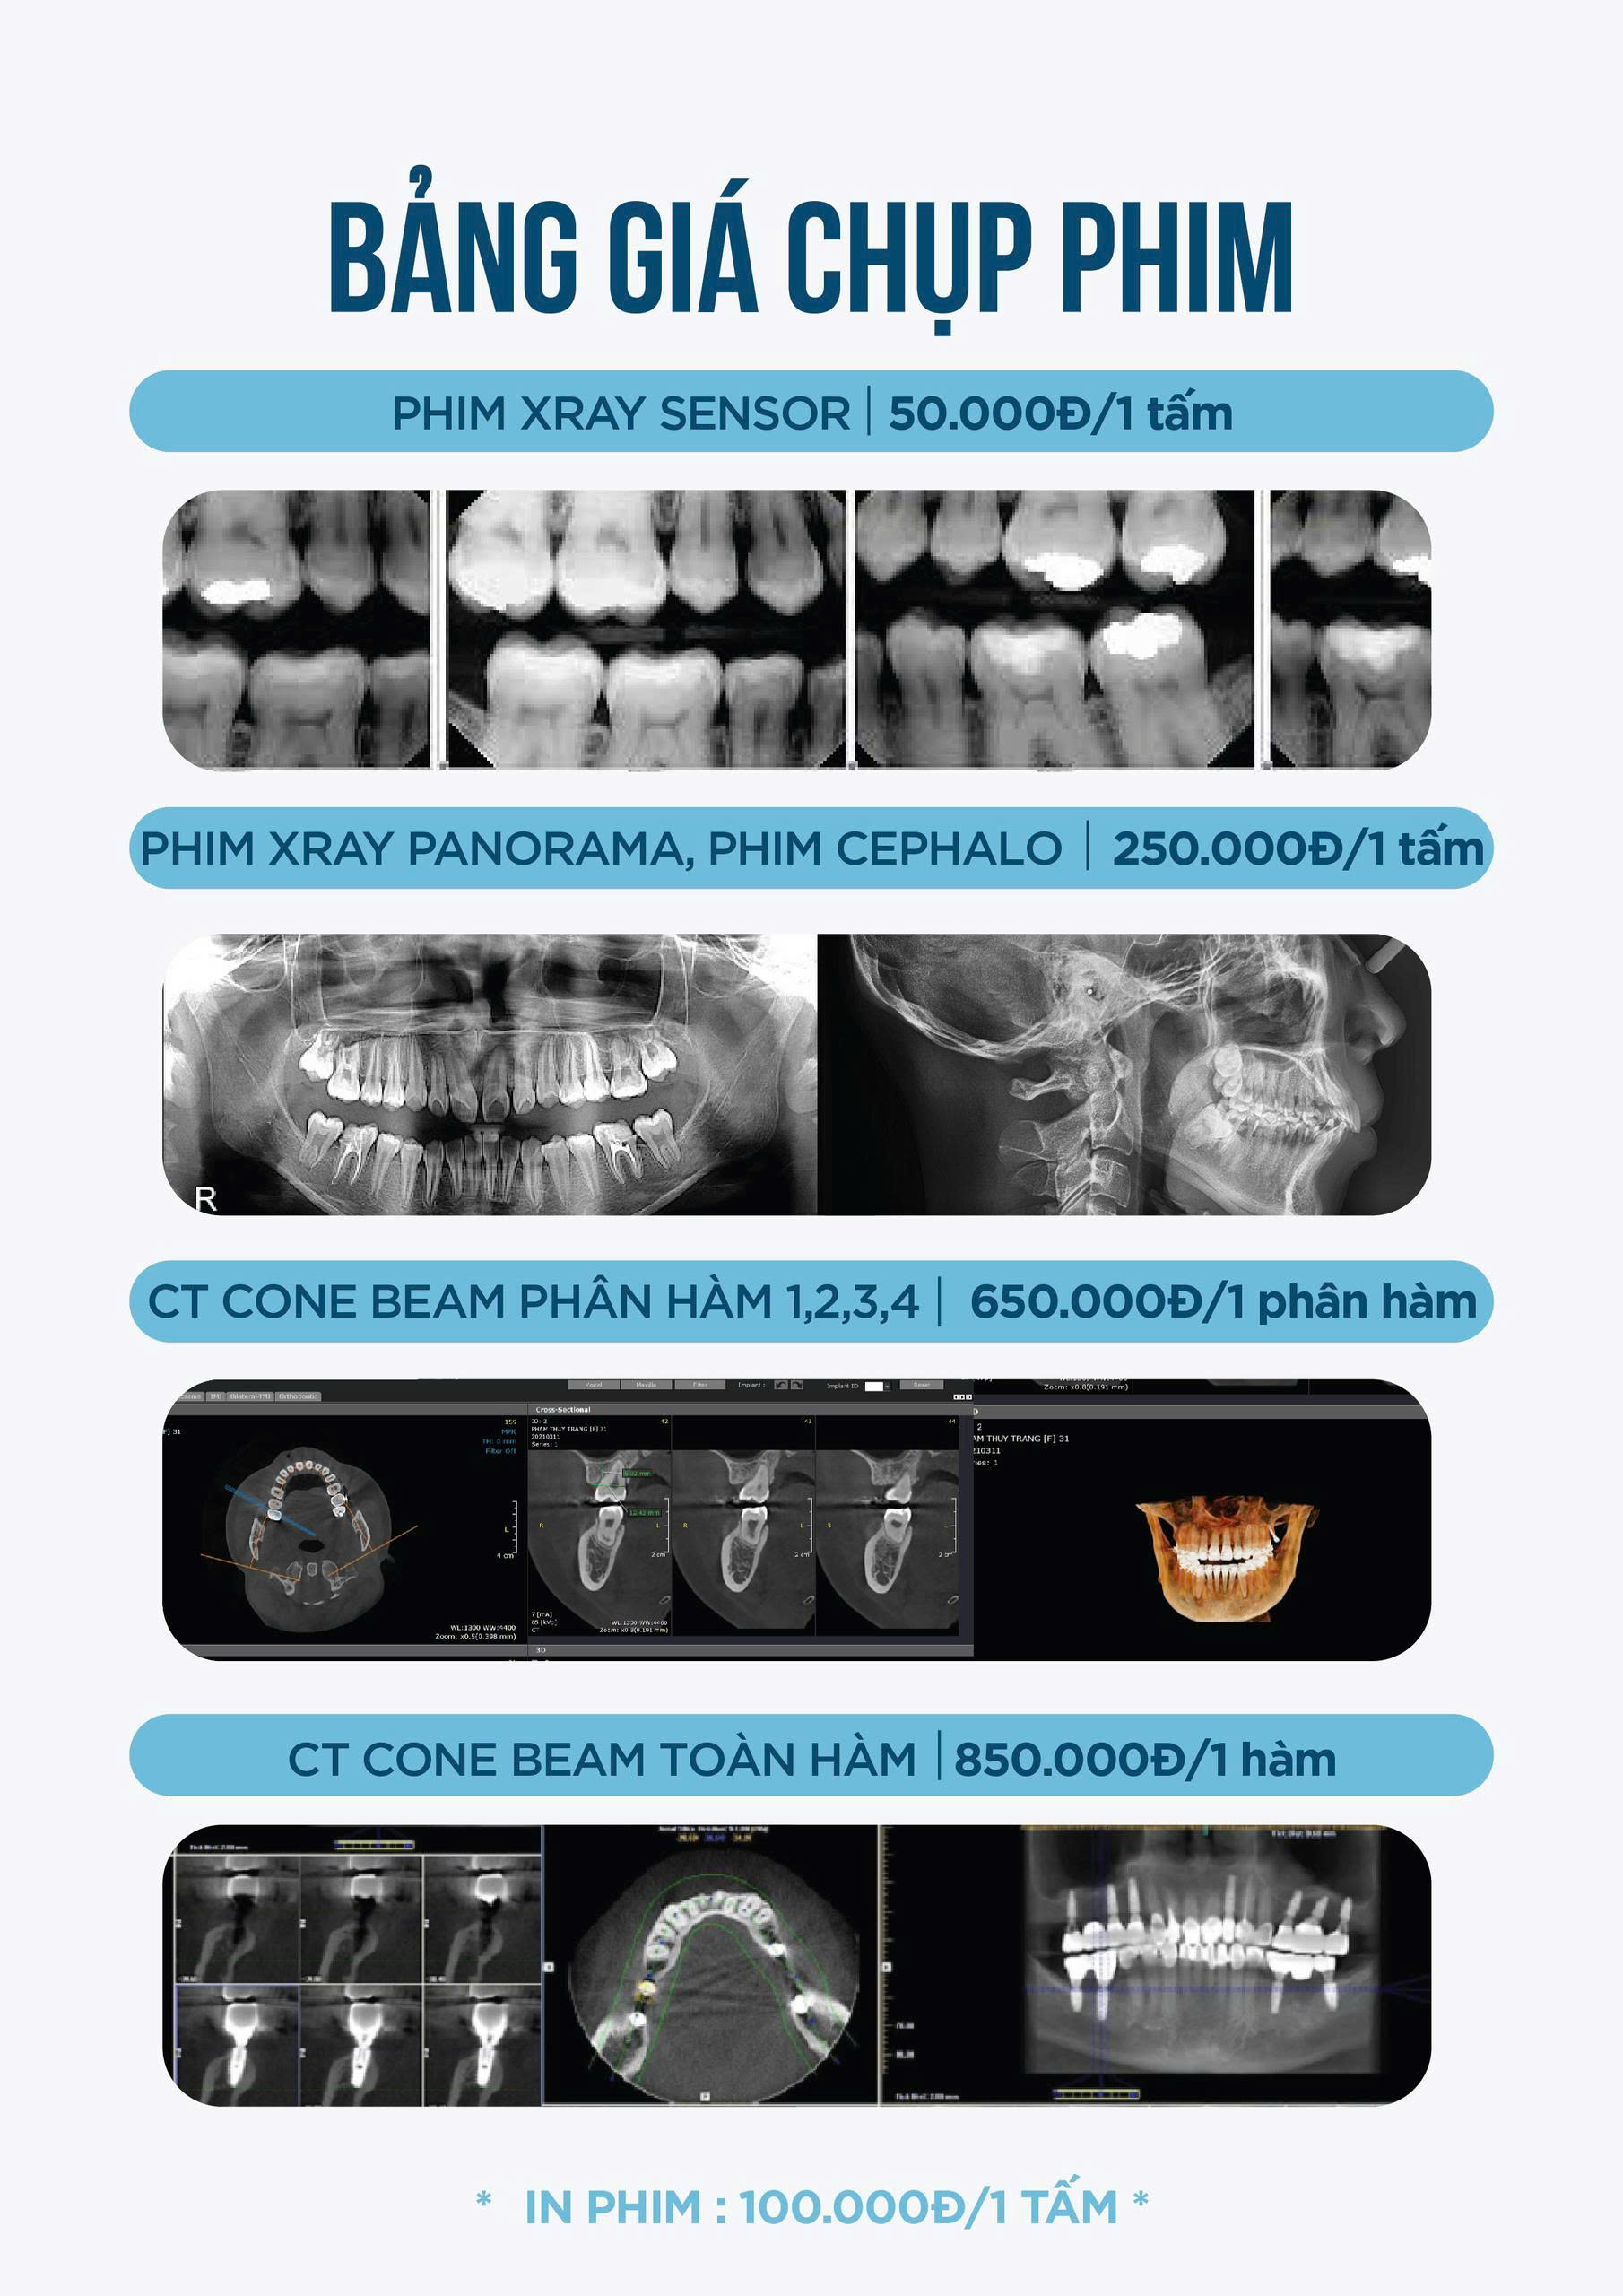

1. Phim X-ray Sensor – Nhanh chóng, rõ nét, hỗ trợ chẩn đoán chi tiết từng vùng răng

Giá: 50.000đ / 1 tấm

2. Phim X-ray Panorama & Cephalo – Toàn cảnh và hỗ trợ chỉnh nha

Giá: 250.000đ / 1 tấm

3. CT Cone Beam phân hàm 1,2,3,4 – Đánh giá chuyên sâu từng vùng

Giá: 650.000đ / 1 phân hàm

4. CT Cone Beam toàn hàm – Hình ảnh 3D toàn diện cho kế hoạch điều trị tổng quát

Giá: 850.000đ / 1 hàm

Chi phí in phim

In phim: 100.000đ / 1 tấm